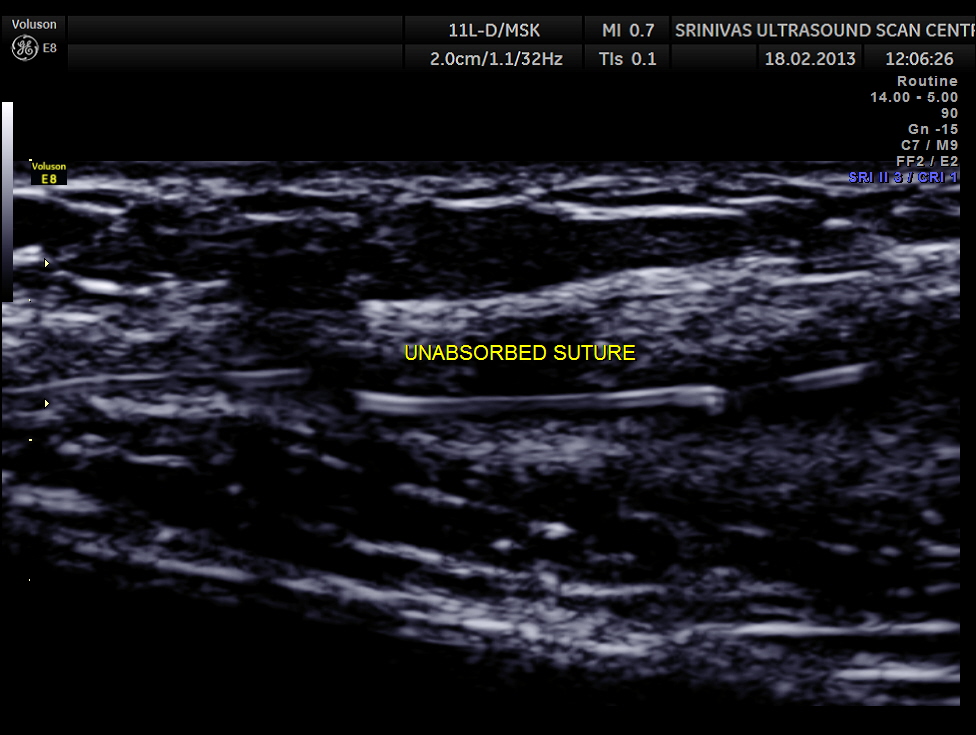

Her routine abdomino pelvic ultrasound scan was normal. The following pictures are acquired with a high resolution 11Mhz transducer.

This revealed unabsorbed suture and irregular collection